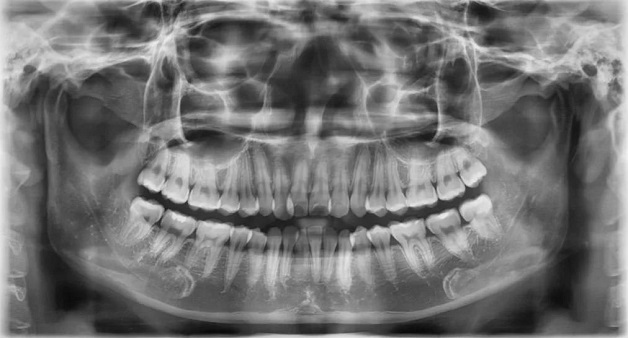

Hình chụp x quang răng.